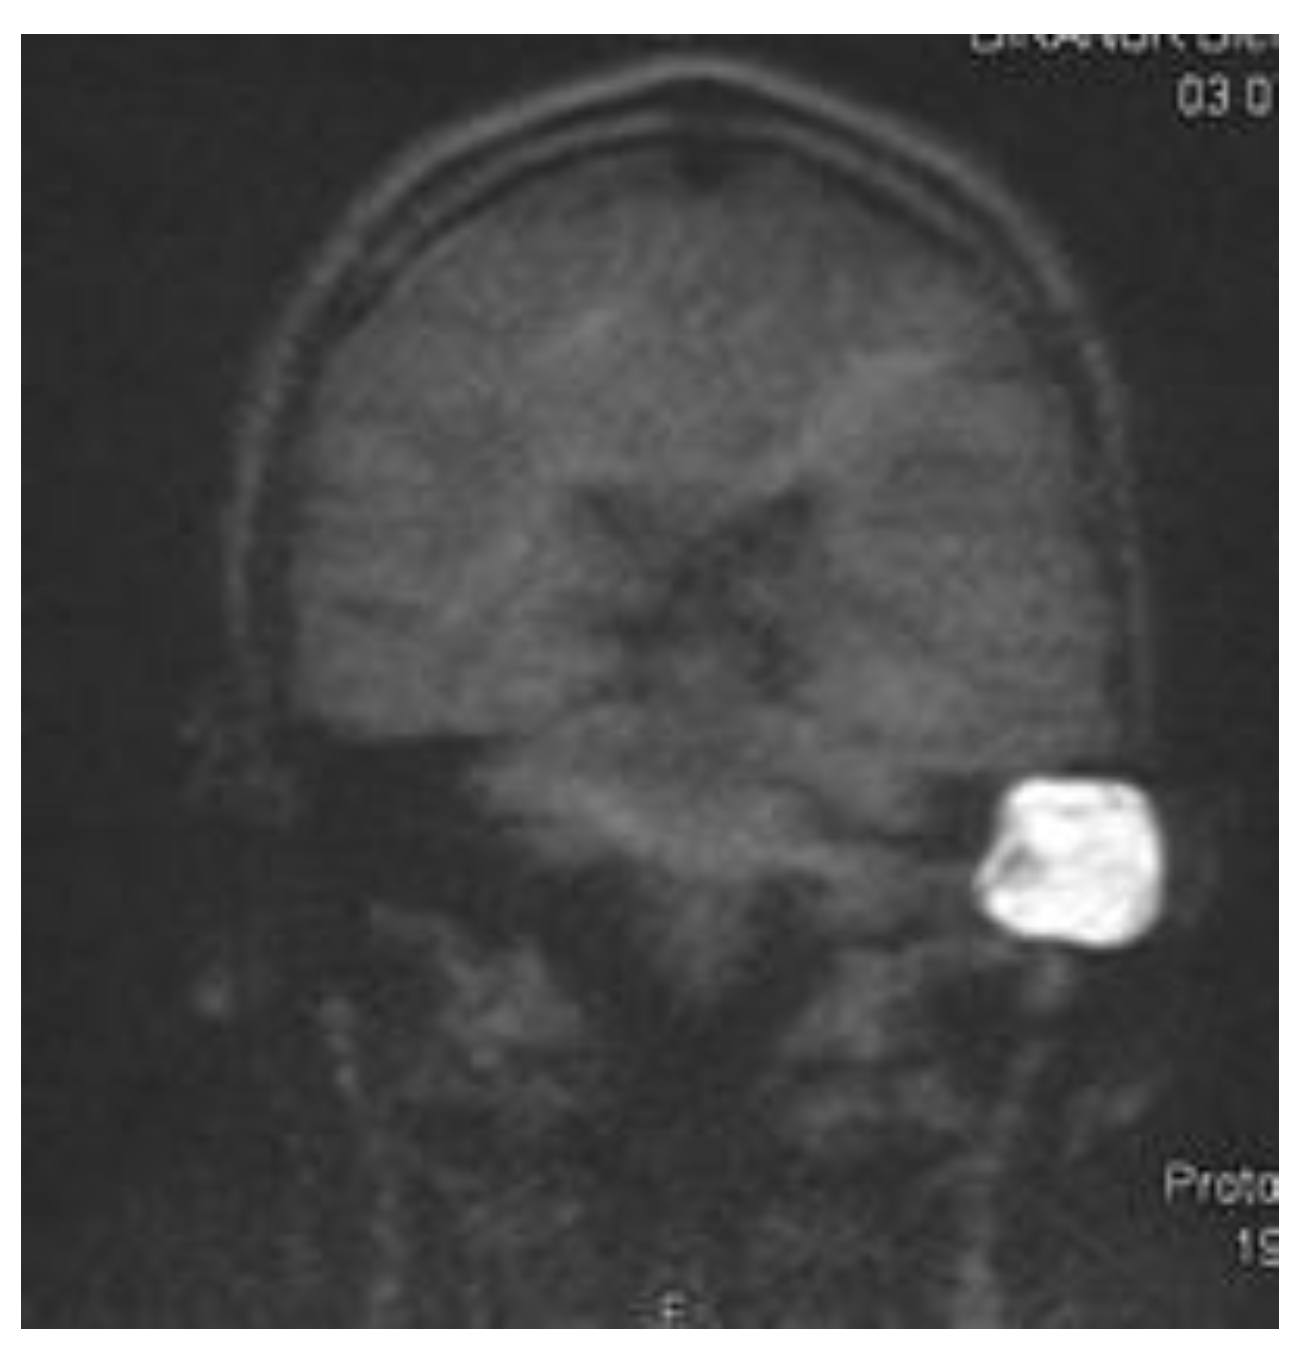

The introduction of MRI into the field of cholesteatoma detection allowed a non-surgical visual second look (Tran ban Huy et al., 1986) for the first time. Besides the initial single-shot echo planar imaging (EPI) DWI detection sequence (Fitzek et al., 2002), non-EPI echo planar imaging DWI was developed, achieving higher sensitivity and specificity of 91% and 97%, respectively (Jindal et al., 2011; De Foer et al., 2006). The disadvantage of most cholesteatoma detection sequences is their high susceptibility to magnetic fields. Therefore, significant distortive artifacts can be generated by an implant (Nassiri et al., 2024), which makes the evaluation of cholesteatoma impossible. Although modified cholesteatoma sequences, such as multishot EPI DWI RESOLVE and single-shot non-epi DWI HASTE (Figure 1), are assumed to be less susceptible to magnets with acceptable rates of cholesteatoma detection (Bozer et al., 2024)

Figure 1. Exemplaric cholesteatoma of a left mastoid cavity scan with HASTE at 1.5 T.